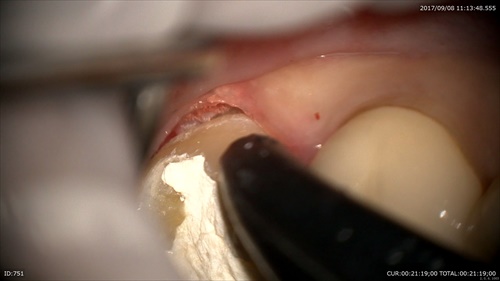

1:根管治療

樋状根でした。

MTAセメントで根管充填